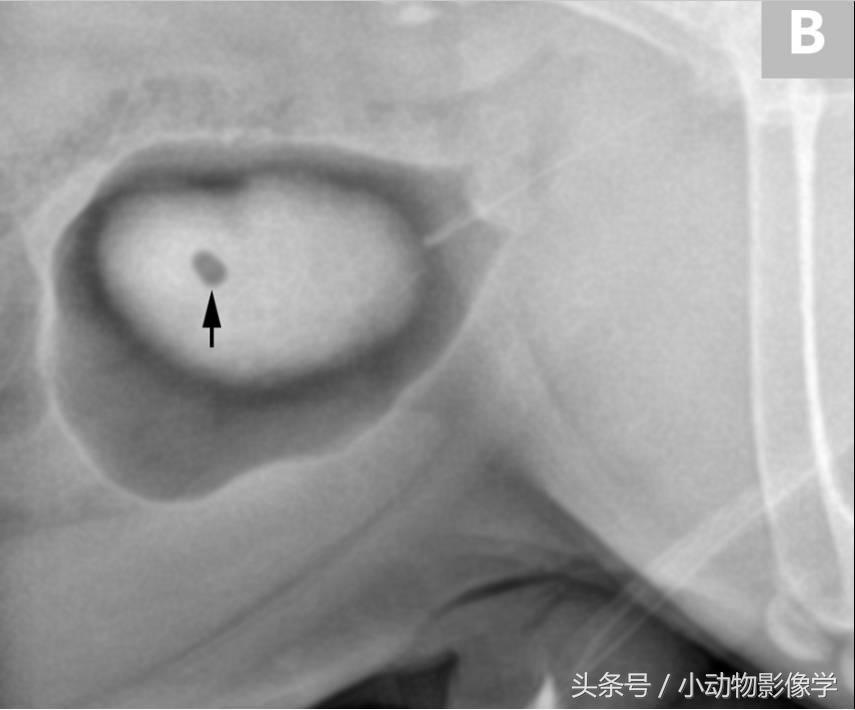

图9A、一只斗牛犬的侧位平片,患犬表现反复的血尿和排尿涩痛。未发现不透明矿物质膀胱结石。

图9B、图9A中患犬的膀胱双对比造影。膀胱中央可见界限清楚、边缘平滑的一处充盈缺损(箭头),符合结石特征。经分析确认为尿酸盐结石。